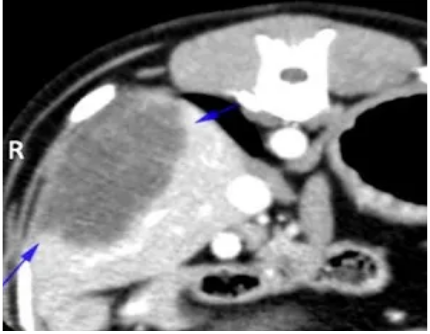

[Uncaptioned image] Dorsal reconstruction contrast enhanced computed tomography image of the abdomen showing the cholangiocellular carcinoma (blue arrows).